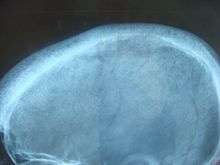

In primary hyperparathyroidism about 75% of people have no symptoms.[2] The problem is often picked up during blood work for other reasons via a raised calcium.[3] Many other people only have non-specific symptoms. Symptoms directly due to hypercalcemia are relatively rare, being more common in patients with malignant hypercalcemia. If present, common manifestations of hypercalcemia include weakness and fatigue, depression, bone pain, muscle soreness (myalgias), decreased appetite, feelings of nausea and vomiting, constipation, polyuria, polydipsia, cognitive impairment, kidney stones (See Foot Note[nb 1]) and osteoporosis.[9] A history of acquired racquet nails (brachyonychia) may be indicative of bone resorption.[10] Parathyroid adenomas are very rarely detectable on clinical examination. Surgical removal of a parathyroid tumor eliminates the symptoms in most patients.

- increased bone resorption, allowing flow of calcium from bone to blood

Primary hyperparathyroidism results from a hyperfunction of the parathyroid glands themselves. There is oversecretion of PTH due to a parathyroid adenoma, parathyroid hyperplasia or, rarely, a parathyroid carcinoma. This disease is often characterized by the quartet stones, bones, groans, and psychiatric overtones referring to the presence of kidney stones, hypercalcemia, constipation and peptic ulcers, as well as depression, respectively.[13][14]